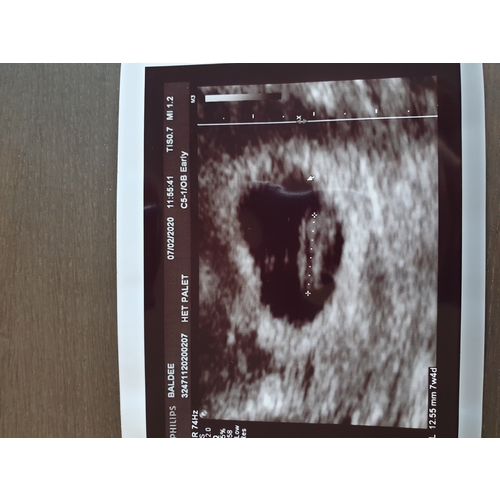

Vandaag ook eerst echo (7 weken en 5 dagen). Alles was goed en lag er goed bij. Ik heb ook weinig symptomen en ben bijvoorbeeld ook niet misselijk. Dit heeft helemaal niks te betekenen. Je moet er juist van genieten zeggen ze :)